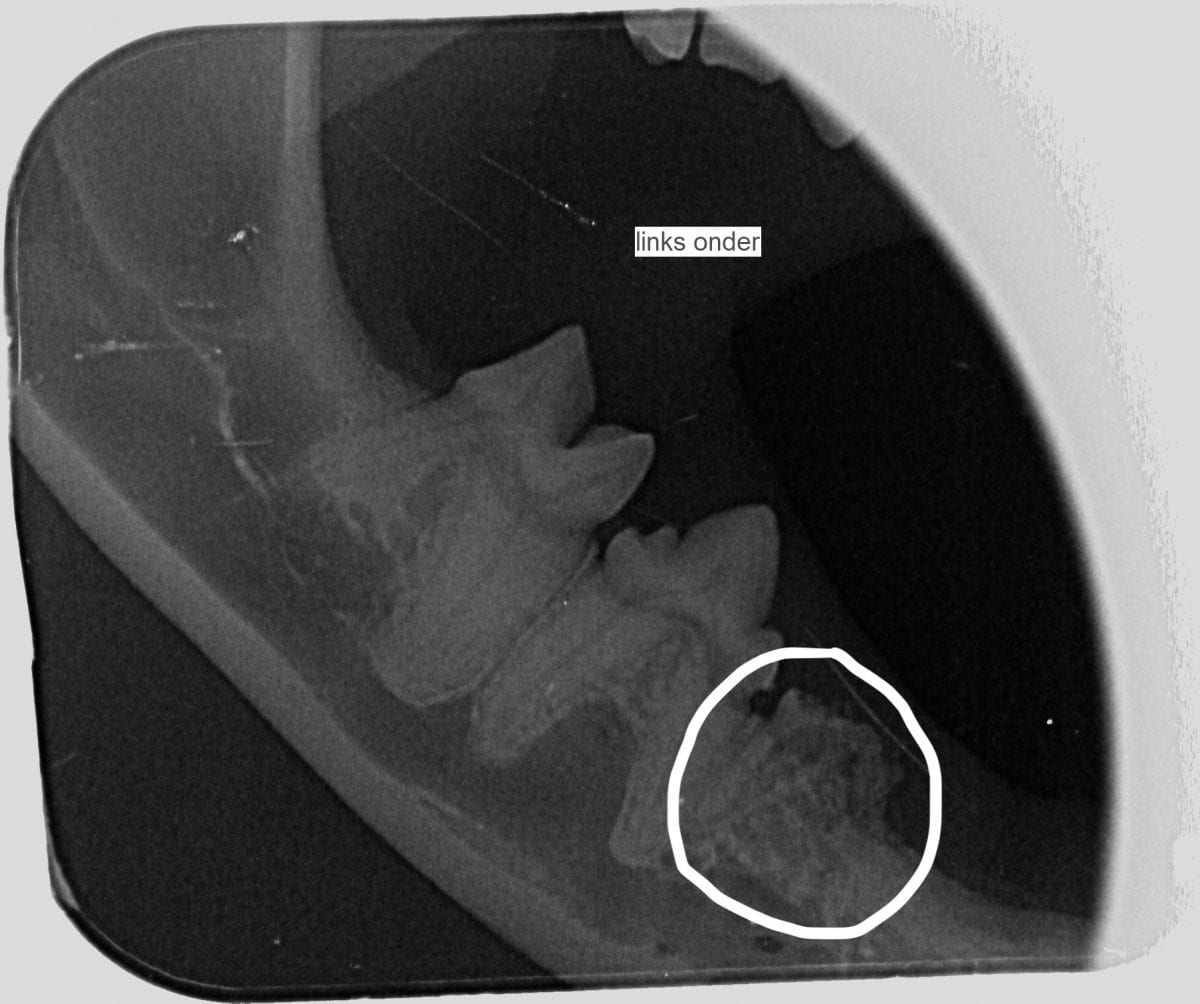

Uw kat krijgt eerst narcose en pijnstilling. Daarna maken we bij katten altijd dentale röntgenfoto’s! De eerder genoemde resorptie letsels komen soms alleen voor in de wortels en zien we dus alleen met een röntgenfoto. Soms is de wortel zelfs al zo opgelost dat alleen de kroon van de tand verwijderd moet worden.

Onderaan deze pagina staan 2 dentale röntgenfoto’s. Op de eerste foto hieronder zie je een kies die al bijna helemaal opgelost is. De foto ernaast laat een kies zien waarbij de wortels nog aanwezig zijn.